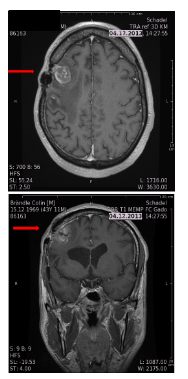

Alpha should not damage neurons, proof of concept: direct injection into motor cortex Can tumor cells infiltrating a functionally critical area of the brain be safely targeted?

Risk of damaging neurons?

Ratio astrocytes to neurons ≈ 10:1

Range: beta 1-5mm alpha: 0.08mm

Alpha particles do not destroy adjacent neurons Minimal damage possible (subclinical) Alpha particles suitable to target functional areas Caveat: repetitive injections, pre-treatment